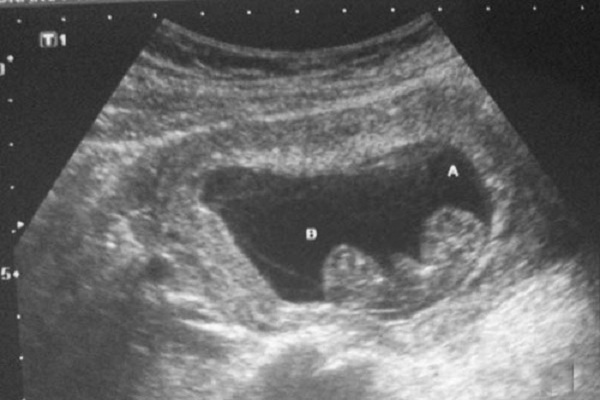

Sàng lọc trước sinh ở tuần thai thứ 7 chưa mang lại kết quả chính xác

Khi thai nhi ở tuần tuổi thứ 7, mẹ duy trì lịch siêu âm định kỳ để bác sĩ kiểm tra kích thước phôi thai, nghe tim thai, xác định vị trí và nguyên nhân xuất huyết nếu có, đảm bảo phôi thai có bám chặt vào thành tử cung hay không,...